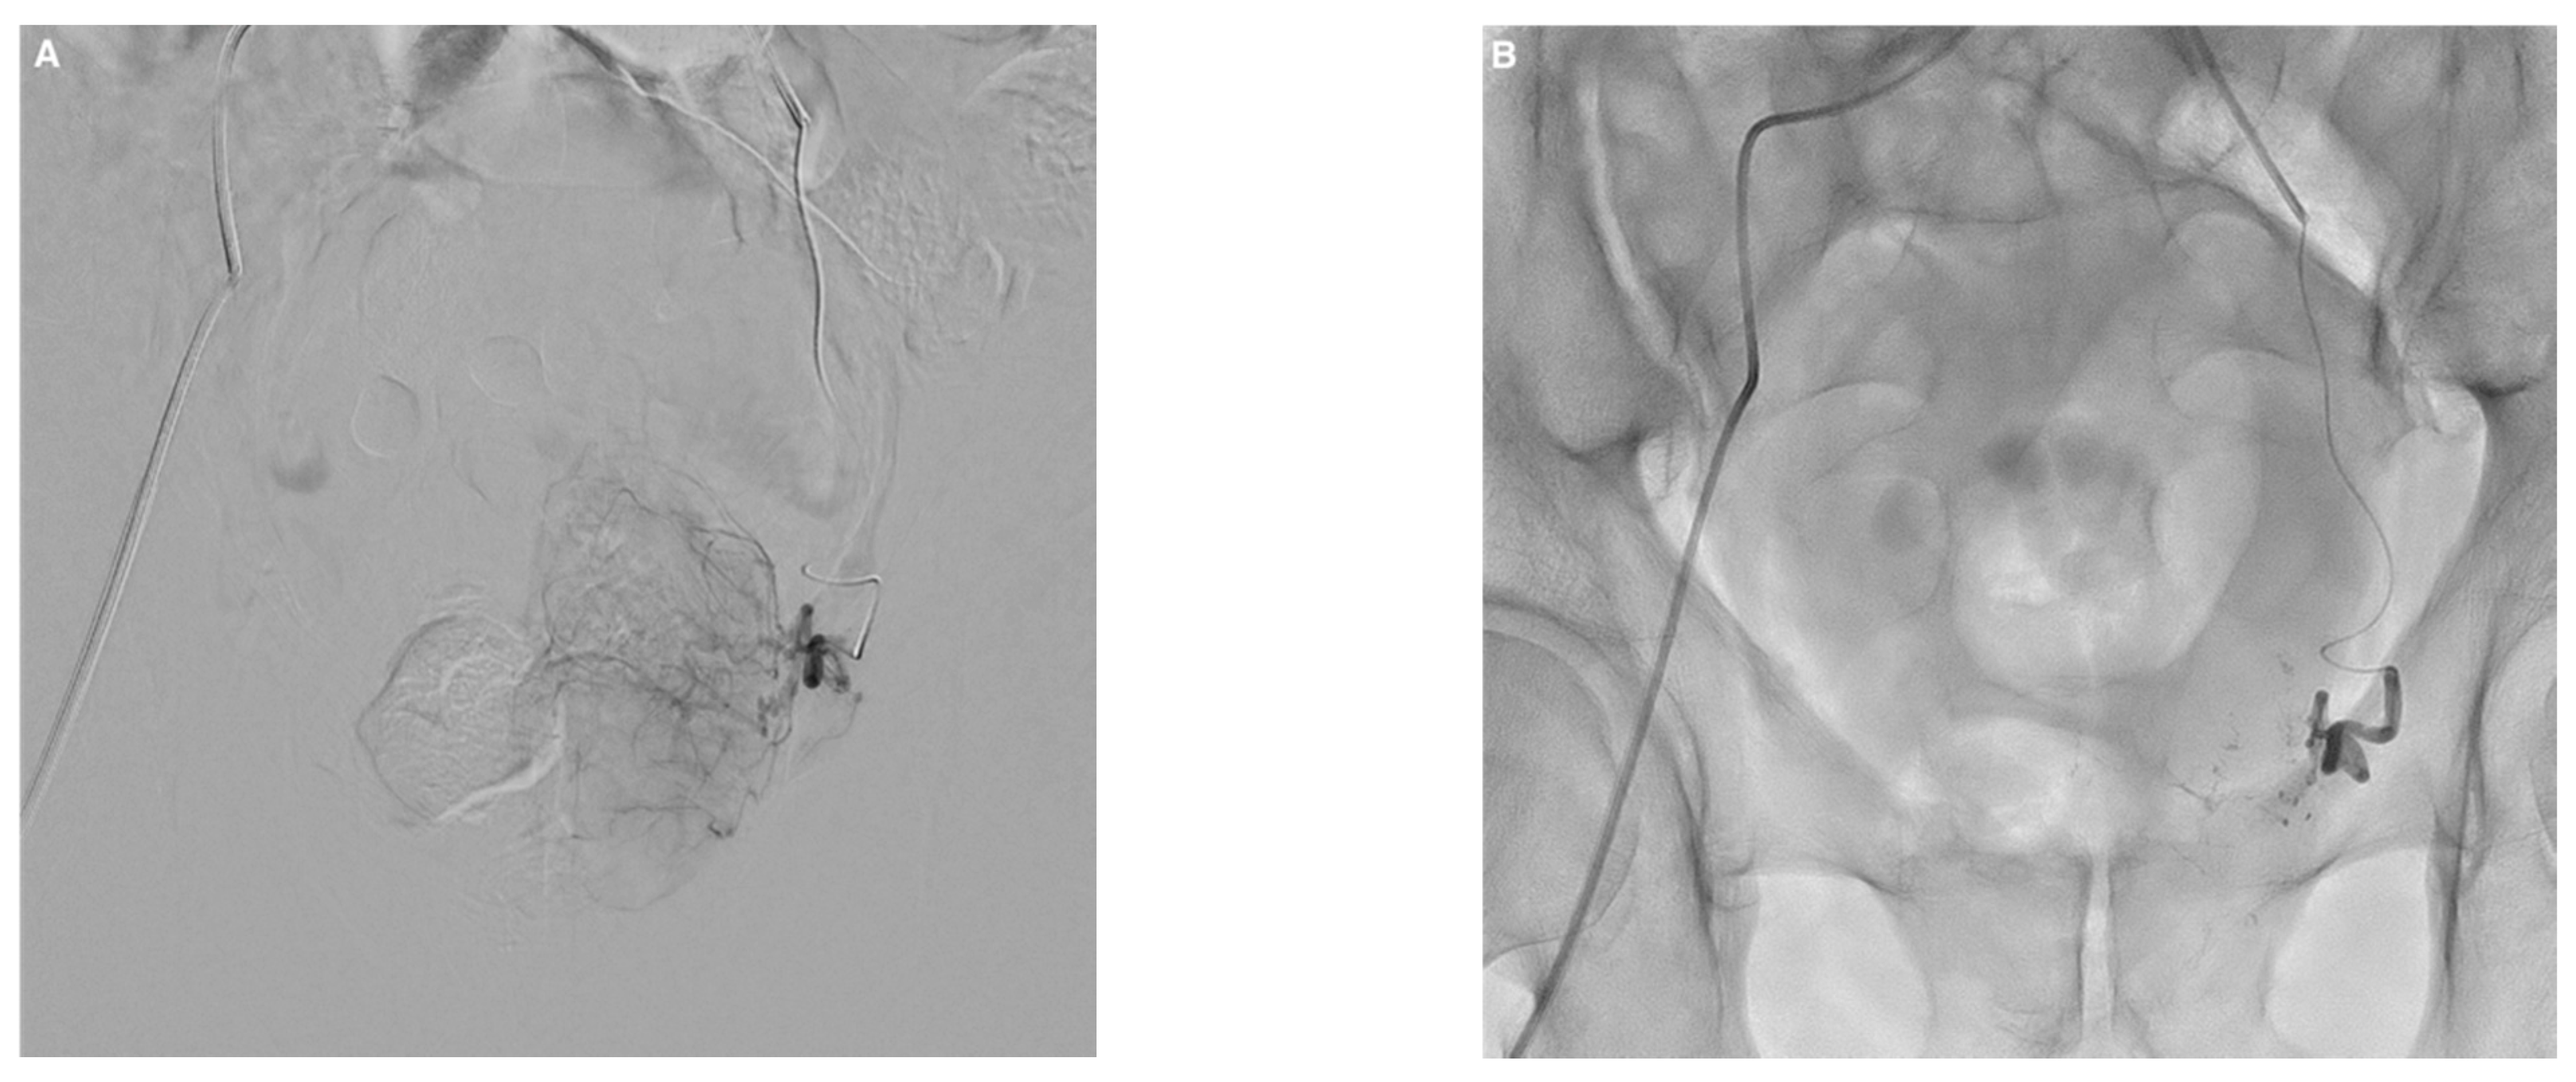

JCM Free FullText Prostate Artery Embolization Using NButyl

From www.mdpi.com

JCM Free FullText Prostate Artery Embolization Using NButyl Glue For Embolization A fibrin glue kit consists of separate solutions of fibrinogen and thrombin that instantly coagulate when mixed together and. In contrast to particulate or coil embolics that physically obstruct blood flow, liquid embolics can induce embolization via. A clinical study, compromising 31 patients with cerebral avms, demonstrated that glubran 2 can be used for the curative embolization of avms with. Glue For Embolization.